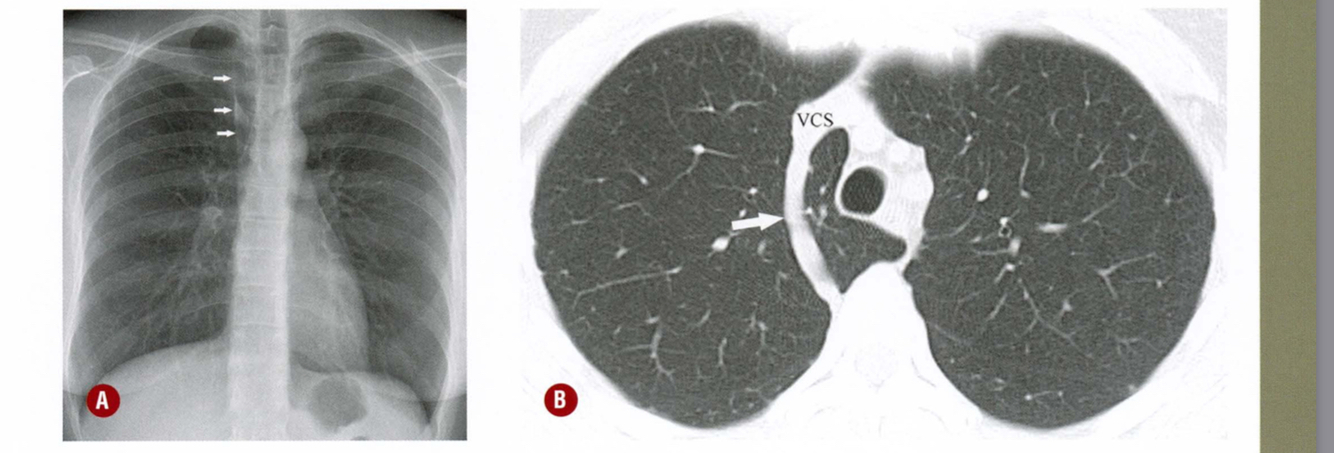

Descreva as fissuras apontadas pelas setas e os lobos pulmonares